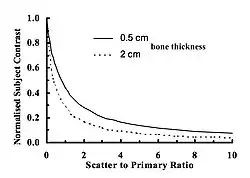

- where SPR is the ratio of the scattered to primary radiation intensities - the so-called Scatter-to-Primary Ratio. Note that the simple, non-scatter, linear relationship can be obtained when the SPR is set to zero in the above equation.

- The SPR can therefore be considered to be reasonably large in many clinical radiographs to an extent that scatter can be considerably higher in intensity than that of the transmitted primary beam which contains the radiographic attenuation information. Another perspective on this situation is shown in Figure 3.17. Here, the influence of SPR on the subject contrast of two thicknesses of bone are shown. It is seen that the even a small amount of scatter can have a significant effect on contrast. For instance, the contrast of a 2 cm thickness of bone is seen to be reduced by 50% when the SPR is just 0.6 and by about 90% when the SPR is equal to 2. We can therefore infer that even an SPR of just 2, as has been measured in the lung fields in CR chest radiography, can have a substantial influence on the contrast of attenuating lesions within those fields. It can therefore be concluded that contrast in radiographic images can be improved substantially when scattered radiation is reduced, i.e. when the SPR is improved.